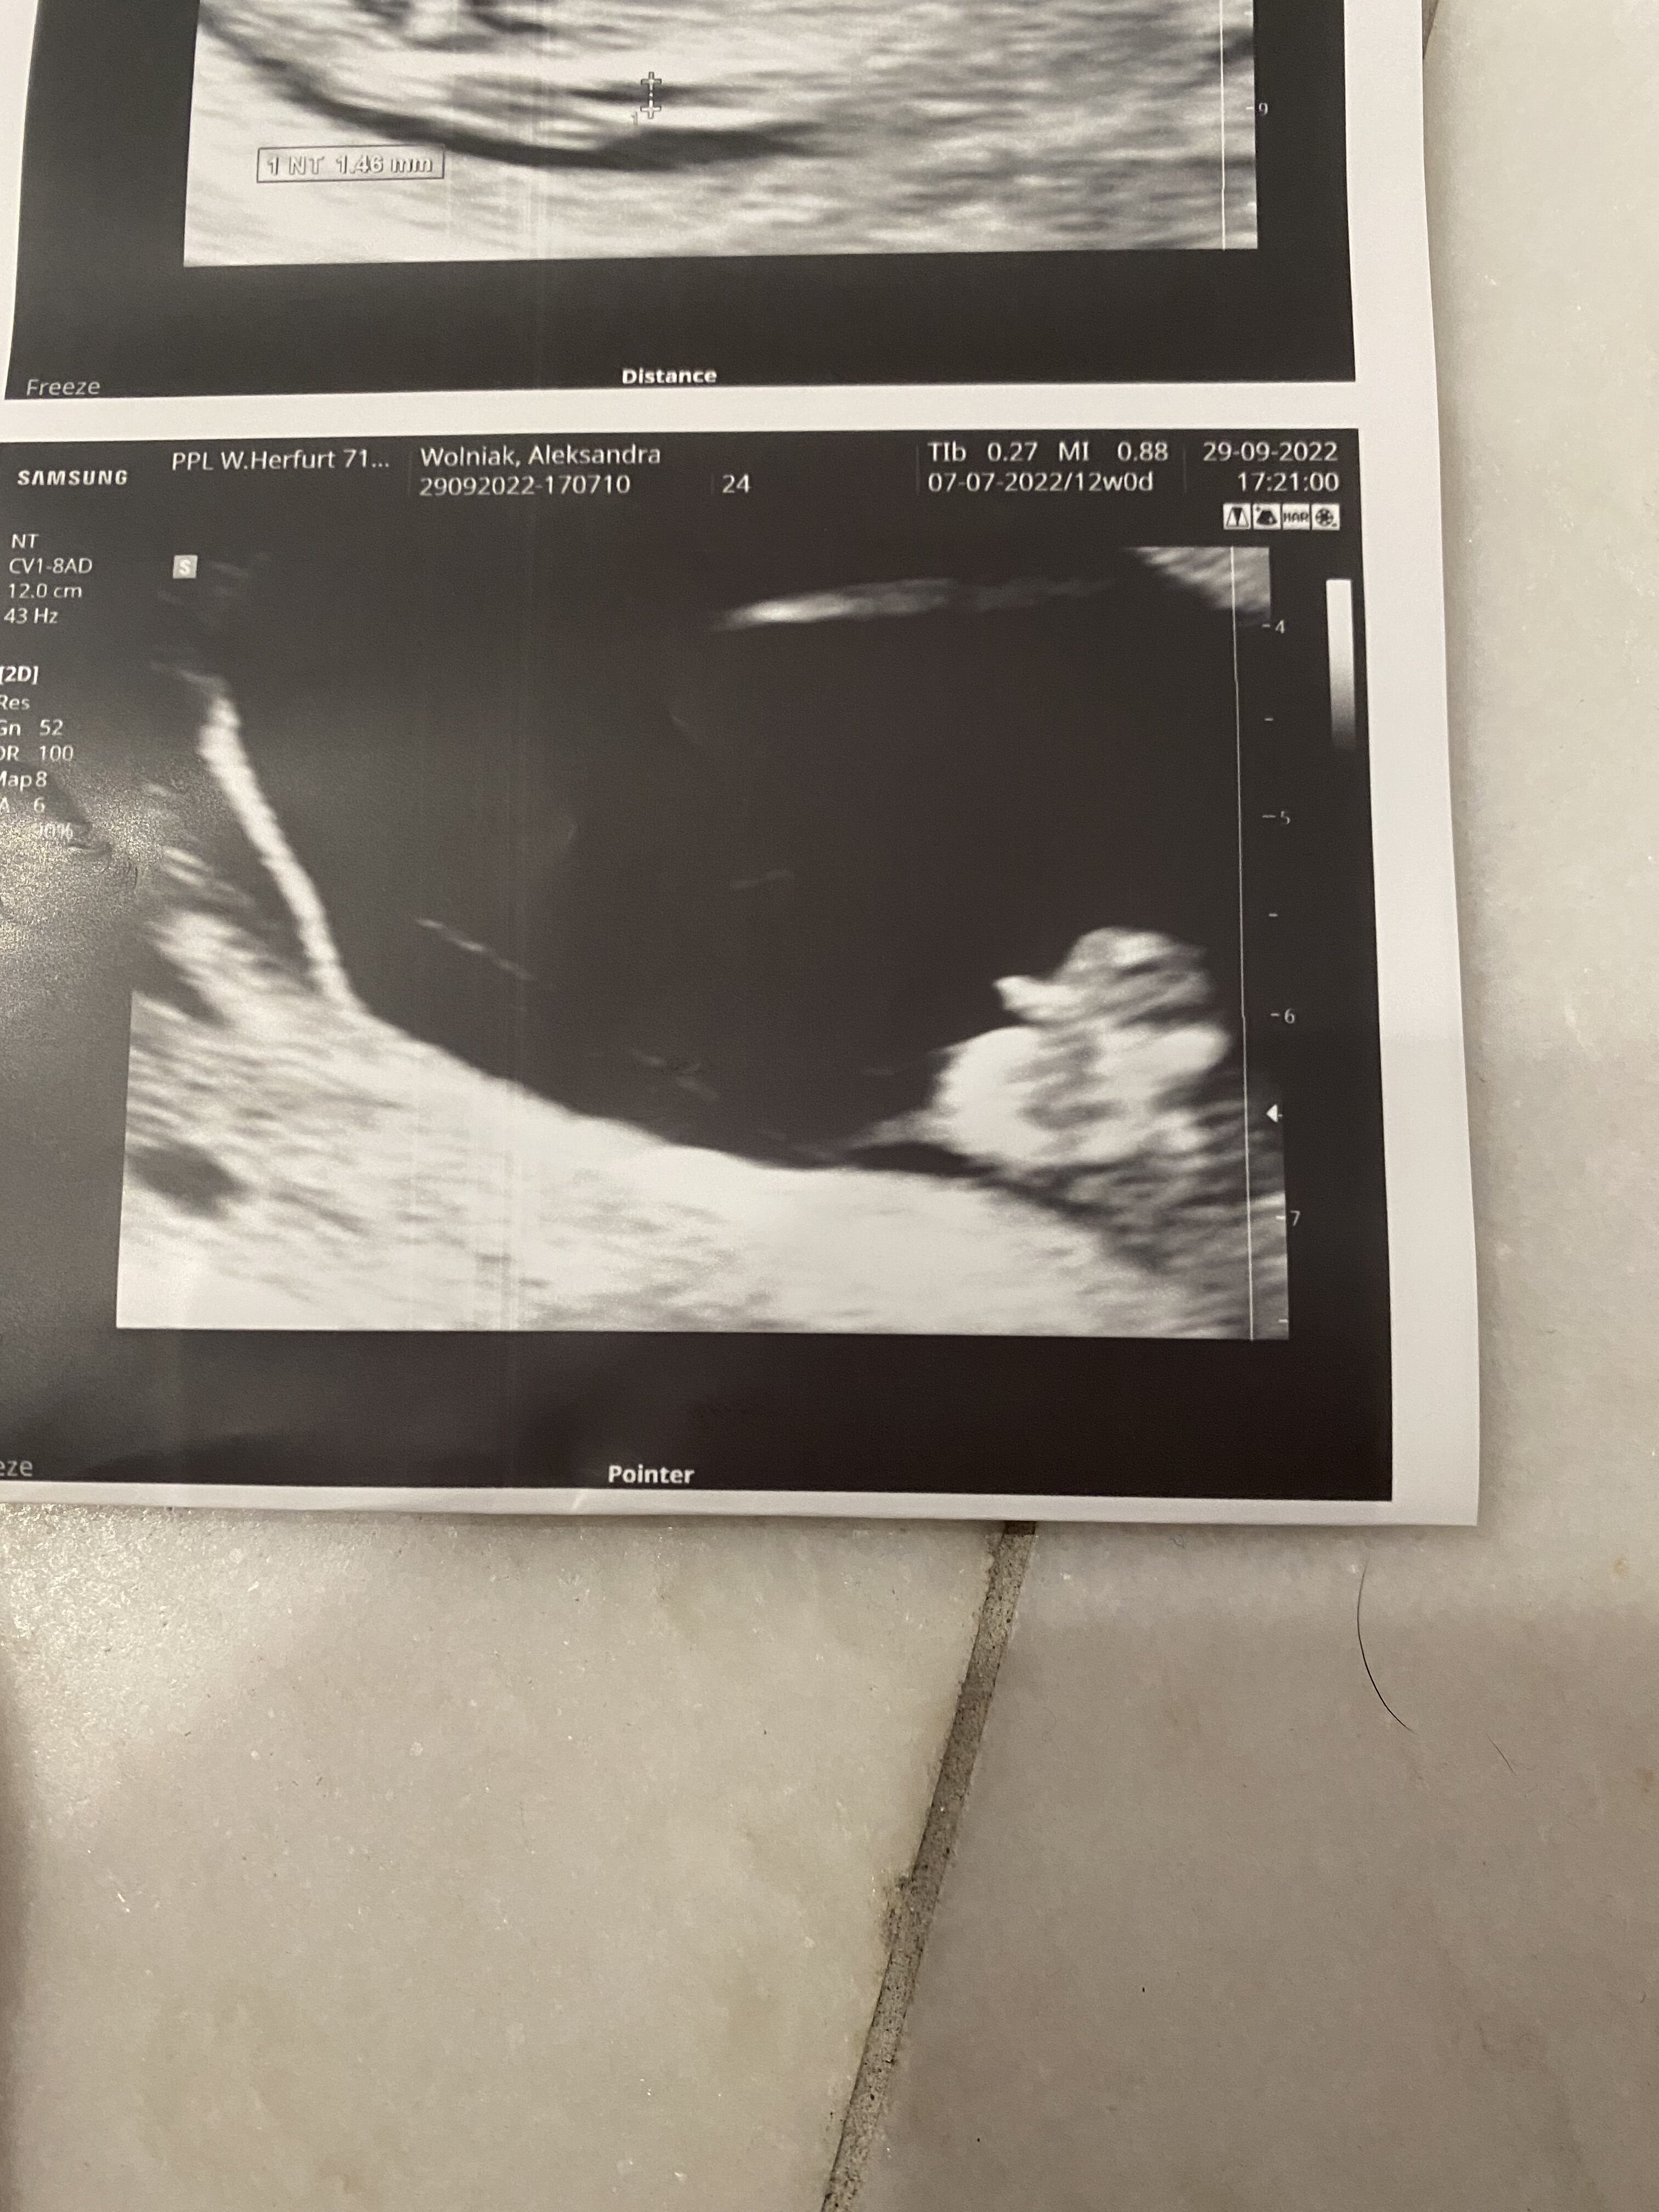

Chłopak czy dziewczynka?

W 13 tygodniu lekarz mówił że raczej chlopczyk

• Screenshot_20230325_120326_Gallery.jpg

Screenshot_20230325_120326_Gallery.jpg

236,5 KB · Wyświetleń: 151

• Screenshot_20230325_120412_Gallery.jpg

Screenshot_20230325_120412_Gallery.jpg

290,7 KB · Wyświetleń: 156